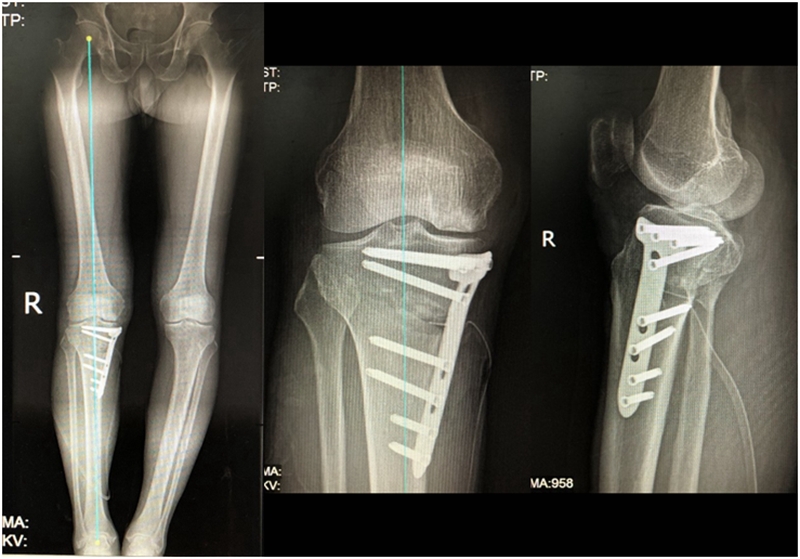

最终选择截骨矫形

术后1年1个月

视频1 自由行走,临床效果佳

视频2 术后1年6个月,自由行走,临床效果佳

术后2年1个月拆钉

视频3 关节镜探查+拆钉,外侧间室 Outerbridge Ⅱ度

视频4 内侧间室 Outerbridge Ⅲ-Ⅳ度

内侧半月板突出未见明显进展

病例1:男,64岁,主诉左膝关节内侧疼痛6年余。MR提示骨坏死区占比为33.28%,矢状位病变区域前后径为26.42mm,半月板相对突出百分比(RPE)31.78%,同时存在胫骨侧来源的下肢内翻畸形(MPTA83°),关节线会聚角2°。

行关节镜检查+软骨摘除+微骨折+HTO术,术后随访2年恢复良好,活动自如,行走时无左膝关节疼痛不适。